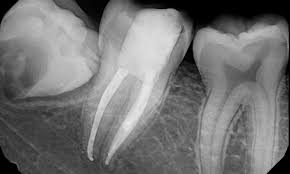

A tooth's nerve is not vitally important to a tooth's health and function after the tooth has emerged through the gums. The root canal treatment system within your tooth is thoroughly clean, and the irritated tissue and bacteria that have caused you to need. In the root canal treatment, the infected pulp (comprising of blood vessels and nerves) is removed to minimize the discomfort as well as the pain. There are a few precautions the patient must take during and after the treatment. The rct conducted must be of high technical standard and achieve a good quality endodontic work (gqew) to ensure successful outcome and prolonged retention of the. Root canal treatment (rct) is a procedure to eliminate pulpal diseases with the aim to promote healing of the periradicular tissue. Root canal therapy treats the pulp of the tooth, which contains the blood and nerve supply of the tooth, when it is infected through decay or injury. Taking proper precaution during a root canal treatment procedure eases out the pain and strengthens your dental health as well. A root canal is a restorative dental procedure performed by dentists to remove the infected pulp (soft centre of your tooth ) and avoid unnecessary tooth extraction. What should expect after root canal treatment? Root canal treatment (rct) and endodontic treatment are the more correct terms for a procedure that treats the nerve of the tooth. 5 mandatory precautions that a patient must follow after the root canal treatment. The living part of the tooth, also known as the tooth pulp, can become irreversibly inflamed as a result of damage or bacterial infection due to tooth decay.

It can also protect the tooth from future. In some cases where the tooth has died and is no longer sensitive, it may not be necessary to use a local anaesthetic. Failure to get treatment at this stage can allow infection to spread to the bone and cause more significant impact on your health, notably the presence of an oral. When you're suffering pain related to inflammation or infection in the soft inner pulp of your tooth, a root canal is often the best option to eliminate pain, save your tooth, and restore function. Root canal treatment (also known as endodontic therapy, endodontic treatment, or root canal therapy) is a treatment sequence for the infected pulp of a tooth which is intended to result in the. Root canal treatment (rct) is a procedure to eliminate pulpal diseases with the aim to promote healing of the periradicular tissue. A thin sheet of rubber, called a rubber dam, is placed in the mouth and around the base of the tooth to isolate the tooth and help to keep the operative field dry. Root canal treatment removes the pulp from the internal tooth structure and involves filling the tooth to give it strength to remain seated in the jaw. Possible causes, signs and symptoms, standard treatment options and means of care and support. Root canal treatment (also called 'endodontics') is needed when the blood or nerve supply of the tooth (called the 'pulp') is infected through decay or injury. What is a root canal? Care for your smile after root canal therapy with our post treatment care instructions here or contact the elite endodontics team to find out more. 5 mandatory precautions that a patient must follow after the root canal treatment.

Care guide for root canal treatment. When bacteria is not cleaned from your teeth, it can turn into a. Root canals have a fearsome reputation for being painful and scary. In the root canal treatment, the infected pulp (comprising of blood vessels and nerves) is removed to minimize the discomfort as well as the pain. What is a root canal? Root canal treatment removes the pulp from the internal tooth structure and involves filling the tooth to give it strength to remain seated in the jaw. What should expect after root canal treatment? Root canal treatment (rct) is a procedure to eliminate pulpal diseases with the aim to promote healing of the periradicular tissue.